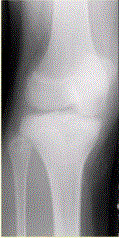

问题 患者男,15岁。右膝X线平片和CT检查见下图。 对于此病变的征象,描述不正确的是

选项 A.右胫骨内侧平台近关节面下不规则溶骨性破坏 B.边缘可见硬化缘 C.病灶内可见多发细小点状钙化 D.可见骨膜反应 E.病变为偏心性生长

答案 D